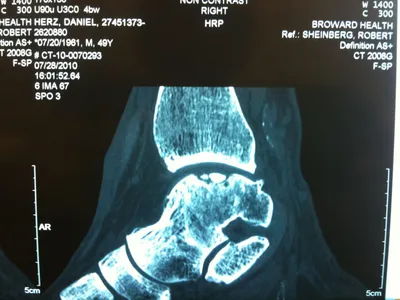

A series of intraop ankle arthroscopy pics of synovial chondromatosis with OCD talus and tibia and microfracture.

Pic of an OCD in the talar dome due to pressure from the nodule.